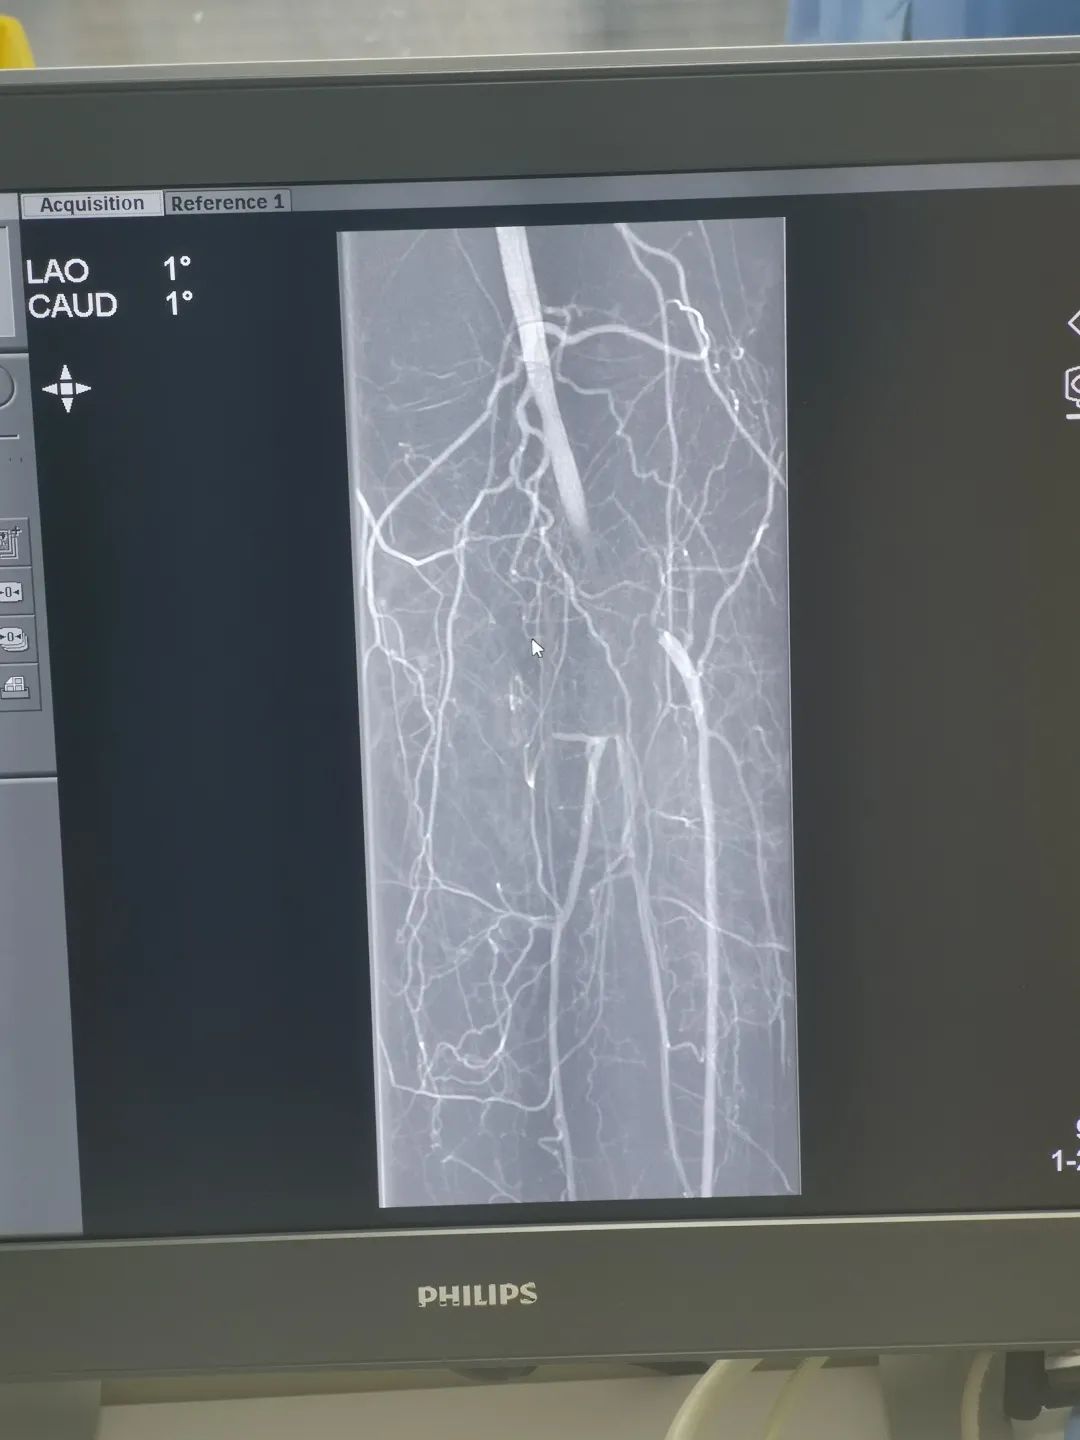

肖阿姨以急诊绿色通道收入院,1 月 19 日 16 点,疮疡血管外科王雷永主任带领王彦辉、刘春阳医生对患者进行急诊介入手术治疗。术中予患者行左下肢动脉造影,左侧腘动脉球囊扩张成形术及置管溶栓术,术后患者左下肢疼痛症状改善,皮温恢复正常,下肢动脉搏动良好,复查造影提示左侧腘动脉血栓吸收再通,胫、腓动脉再通,我院疮疡血管外科成功完成首例下肢动脉球囊扩张、置管溶栓术。